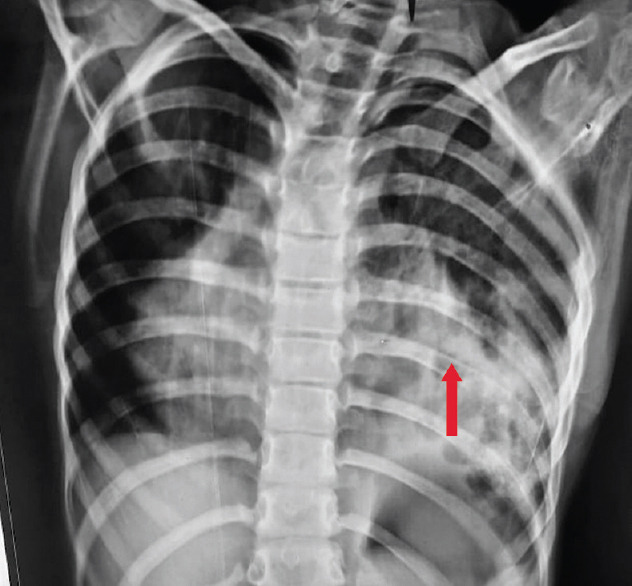

肺动脉闭塞症和囊性肺腺瘤样畸形是罕见的先天性肺囊性疾病。因此,在同一个人身上同时出现这两种疾病的情况非常罕见。肺封闭是一种无功能的肺组织肿块,其血液供应来自肺循环以外的全身血液供应。先天性囊性肺腺瘤样畸形是一种由异常支气管气室和功能性肺泡缺乏组成的肿块。本病例报告了一名 9 岁女孩的病例,她在过去 15 天里出现间歇性发热、左侧胸痛和咳嗽,并且自孩提时代起就反复咳嗽,这提示她患有混合性肺动脉栓塞、先天性肺囊样腺瘤畸形和右心室突出症。

Pulmonary sequestration and cystic pulmonary adenomatoid malformation are rare congenital cystic disorders of the lungs. The presence of both the diseases in the same individual is therefore very uncommon. Pulmonary sequestration is a nonfunctional pulmonary tissue mass that derives its blood supply from systemic blood supply other than pulmonary circulation. Congenital cystic pulmonary adenomatoid malformation represents a mass consisting of abnormal bronchiolar air spaces and a deficiency of functional alveoli. This is the case report of a 9-year-old girl with intermittent fever, left-sided chest pain, and cough for the past 15 days along with recurrent coughs since childhood suggestive of hybrid pulmonary sequestration, congenital cystic adenomatoid malformation, and dextrocardia.